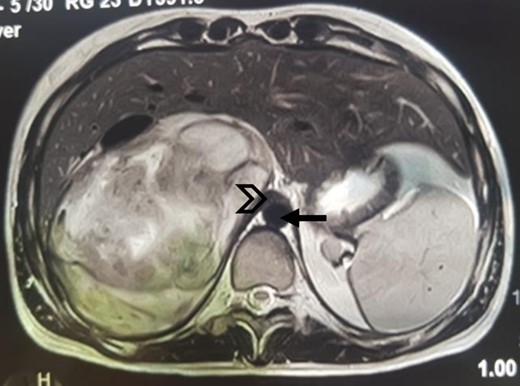

The CT scan incidentally revealed an adrenal incidentaloma in the form of a large right retroperitoneal mass measuring 137 × 101 × 114 mm3, occupying the adrenal cavity, oval, well defined, with regular contours, hypodense, containing areas of fluid density and others of tissue density without significant contrast enhancement, with a wall showing focal thickening of tissue density with low contrast uptake (Fig. 1).

Large right retroperitoneal mass, hypodense, oval, well defined, with regular contours (arrow: aorta; arrowhead: IVC).